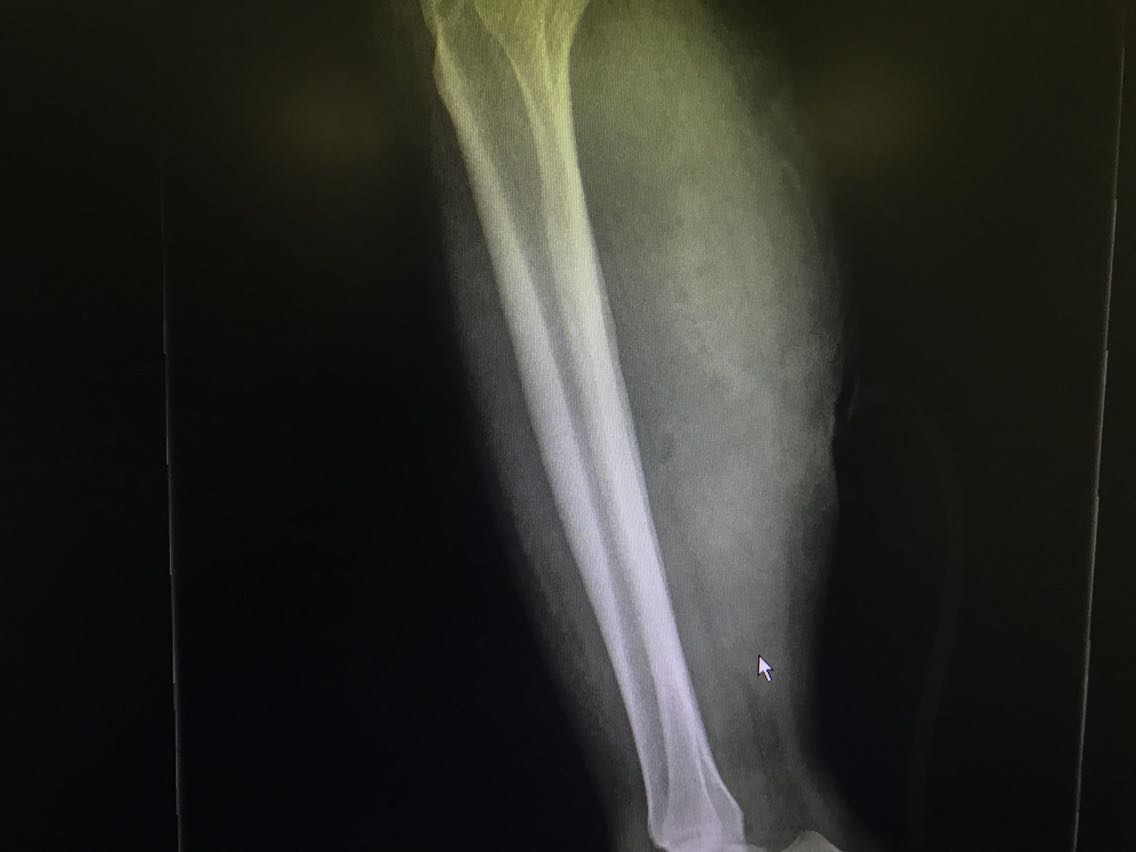

患者女性,54岁。 主诉:车祸伤致右下肢出血伴活动受限18小时。 现病史:18小时前患者乘坐摩托车时被汽车撞击发生车祸,致右下肢开放性损伤,皮肤软组织撕裂,创面出血。无意识障碍等不适。就诊于当地医院,查右下肢DR示:未见明显骨折征象。现为求进一步治疗,就诊于我院,急诊入我科。 既往史无特殊。

查体:右侧小腿中段后内侧见一大小约5*4cm创面,周围软组织肿胀。 辅助检查: 右下肢DR示:未见明显骨折征象。